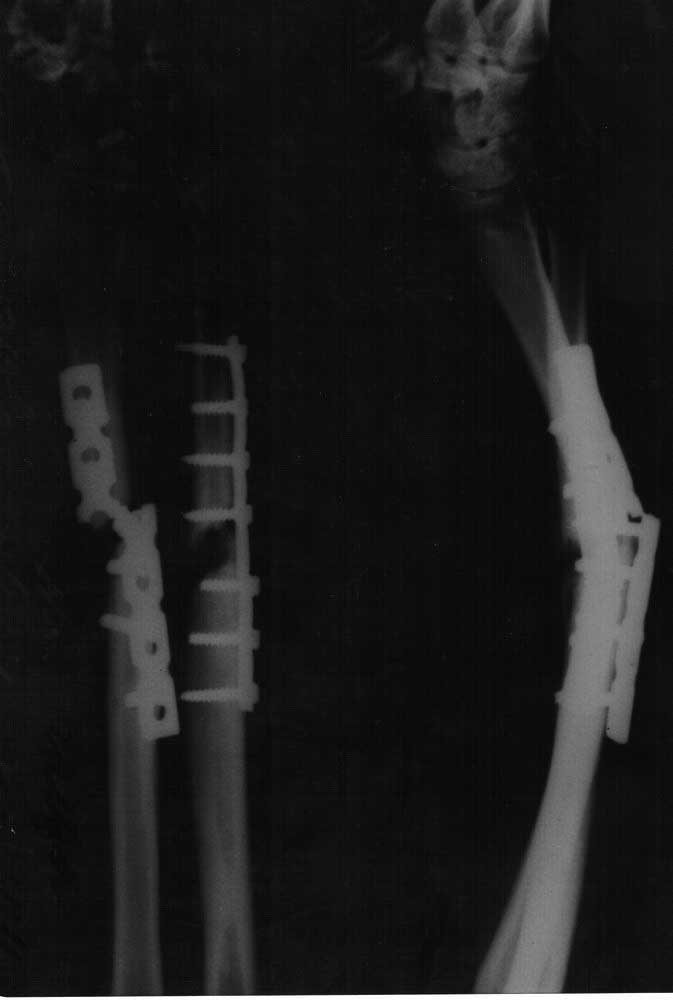

Активно курящая, умеренно пьющая, работающая на сомнительном, но производстве пациентка 37 лет. Заранее извиняюсь, но рентгенограмм предыдущих этапов лечения предоставить не могу (и вряд ли смогу в дальнейшем). Пациент из другого города. Первичная травма - закрытый перелом 22 - В3. Далее МОС (5 мес назад), результат которого Вы видите. Местно - кисть отечна, но безболезненна. Движения (кроме ротационных) - незначитлеьно ограничены. Рубцы без грубого воспаления, хотя отек и гиперемия есть. Вопрос - как делать? В выборе имплантов крайне ограничены, сама ничего интересного не потянет. Нам считается предпочтительным (после того как все убрать и освежить) - укоротить, перевести в простые поперечные переломы и максимально стабильно синтезировать (пластинами)(с какой начать? насколько укоротить?). Попутно вопрос по головке локтевой... Еще раз извиняюсь - пока снимки только такого качества и укладок.

Уважаемый коллега! На мой взгляд, если укорачивать до дефект будет сантиметров по 5 с каждой стороны. Я бы сделал-удалил фиксаторы, обработал бы костные отломки до "кровянной росы"-вскрытие костно-мозговых каналов, декортикация+ взятие костных трансплантатов из гребня подвздошных костей и фиксация LCP 3,5 (или другой пластиной которая в наличие. По поводу головки локтевой трудно сказать (снимки не ахти), но думаю при восстановлении оси встанет на свое место, если нет, то фиксация радиоульнарного сочленения 2 винтами. Есть опыт лечения подобных ситуаций, выходили таким способом-срасталось. Удачи!

Ничего катастрофического нет. Многие из нас встречались и с более серьёзными ситуациями. Мне кажется, шанс на успех есть, если стараться особо не «заумничать», и не забубнить простите, всё разговорами о, скорее, мнимой инфекции. Это главное. Ведь, если мы говорим о клинически значимой инфекции, то при такой степени несостоятельности фиксации и сопутствующей подвижности всё давно бы проявилось флегмонами или абсцессами. Этого нет. Значит – имеющаяся гиперемия кожи и так далее – всего лишь клинические знаки ложного сустава. Не более того. И, конечно, если понимать, что анатомия диафиза предплечья должна быть максимально восстановлена.

Собственно об операции. Никаких изысков, отличающих данную хирургию от успешной хирургии, допустим, 80х годов прошлого столетия и не нужно. Желательно оставить в покое гвозди и другие глупости. Что нужно? Две 3,5 мм (не реконструктивные, не 1/3 трубчатые, не ½ трубчатые), две нормальные пластины. Те, что, скорее всего, лежат у Вас в столе, там, под бумагами, в марлечке. Именно те, что Машенька (Настя, Катя, Люся – кому как повезёт) отдала из операционной ещё чёрт знает сколько лет назад. Вот они и нужны. Одна на 7 отверстий, или длиннее чуть. Другая на шесть... Или так же на 7. Не надо никакого блокирования! Обычные компрессирующие, или даже (прости, Господи!) с круглыми дырками. 3,5 мм, это – главное. Аутотрансплантаты из крыла. Это очень даже желательно, учитывая остеолизис. Но, не здоровые куски, а, - чипсы и аутоспонгиоза в достатке. Никой резекции! Ни капли! Удаляете металл и широкая декортикация (долото заточить сможете). Под декортиканты и уложить можно аккуратненько ауточипсы и спонгиозу. И пластины, 6 – 7 бикортикальных стандартных винтов в каждую. Никакого гипса и ФТО – нормальная жизнь с первого дня. Пусть дальше курит. С уважением, Андрей